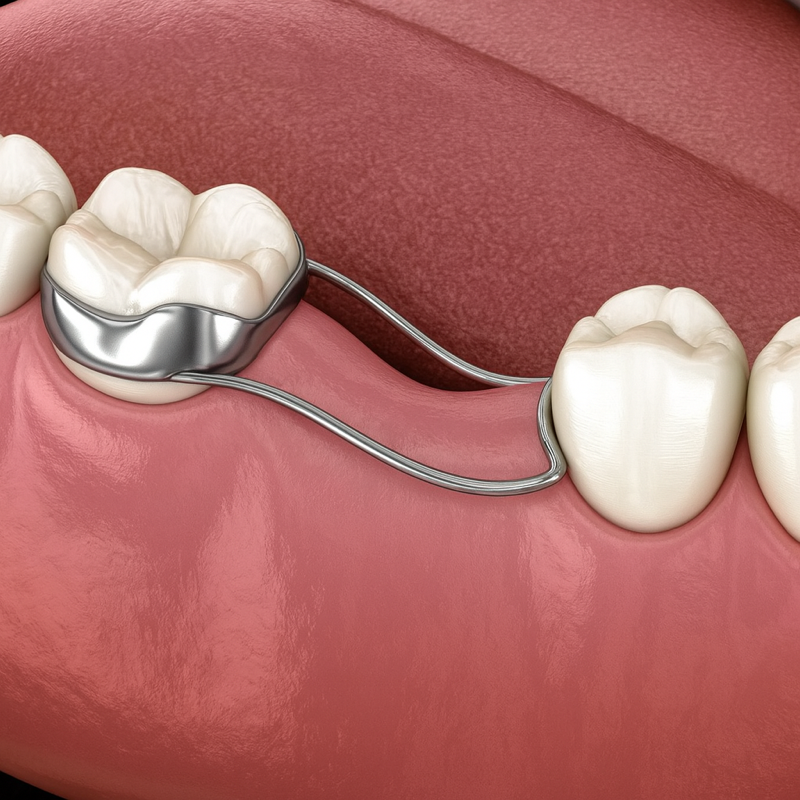

🟧 유치가 하는 가장 중요한 역할:

‘공간 유지’

유치는 그냥 빠지는 치아가 아니고,

영구치의 길을 안내하는

‘공간 지킴이’ 역할을 합니다.

그래서 유치 충치는

“어차피 빠질 치아니까 괜찮겠지”가 아니고,

유치 치료는 영구치 건강을 지키는 첫 단계입니다.

유치가 일찍 빠지면

주변 치아가 공간을 잠식해

영구치가 날 공간 자체가 사라질 수 있어요.